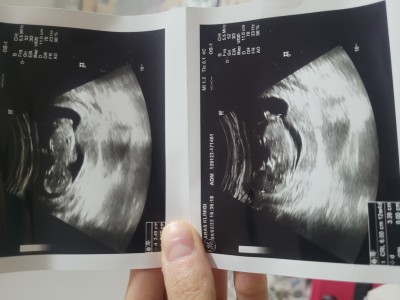

Merhaba arkadaslar rica etsem ultrasona gore cinsiyet tahmini yaparmisiniz.

Gebelik haftası 14+4